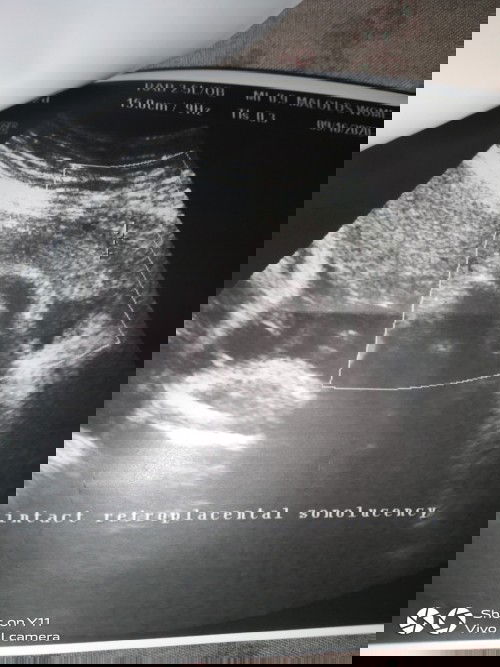

tanong ko lang po kung ano po ibig sabihin nang intact retroplacental sonolucency?im 34weeks tY po

tanong ko lang po kung ano po ibig sabihin nang intact retroplacental sonolucency?im 34weeks at tsaka ma explain nyu po ba sakin itsura nung ultrasounds ko po kung nakaharap po ba sya o naka tagilid po? Thankyou po sa makakapansin godbless po #theasianparentph #pregnancy